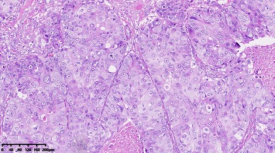

在本项研究中����,研究人员利用基本的组织形态学方法及免疫组织化学法对TNBC进行分型��:腔面雄激素受体型(LAR)(图1A)��,免疫调节型(IM)(图1B)�����,基底样免疫抑制型(BLIS)(图1C)���,间充质型(MES)(图1D)�����。评价各亚型临床病理参数(如发病年龄��、肿物大小���、淋巴结转移等)���,组织形态学(肿物中央瘢痕形成���、浸润模式����、肿瘤间质浸润淋巴细胞���、细胞排列方式���、细胞核形态��、核分裂计数���、间叶化生等)以及免疫表型(p53����、Rb���、PD-L1���、MMR等)�����,结果显示���:1.TNBC分型的临床病理����、组织形态学和免疫表型特征不尽相同���,有望成为复杂的基因表达谱分析的替代选择����,为TNBC的分型治疗及靶向治疗提供理论依据��;2.生物标记物 PD-L1作为重要的生物学指标�����,对个体化治疗及免疫治疗有重要的临床指导价值��;3.乳腺癌中dMMR作为一个低频发生事件��,不太可能作为免疫治疗有效性的评估手段����。该成果发表在Virchows Archiv期刊����,题目为“Subclassifying Triple-Negative Breast Cancers and Its Potential Clinical Utility”��。文章DOI为����:10.1007/s00428-022-03329-0�����。

图1. 基于组织形态学及免疫组织化学标记物的TNBC分型